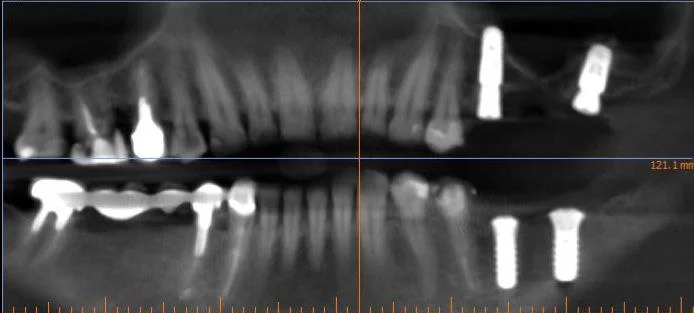

Видалення 4-х зубів, імплантація 4 імплантів Штрауман. Закритий синус-ліфтинг, кісткова пластика.